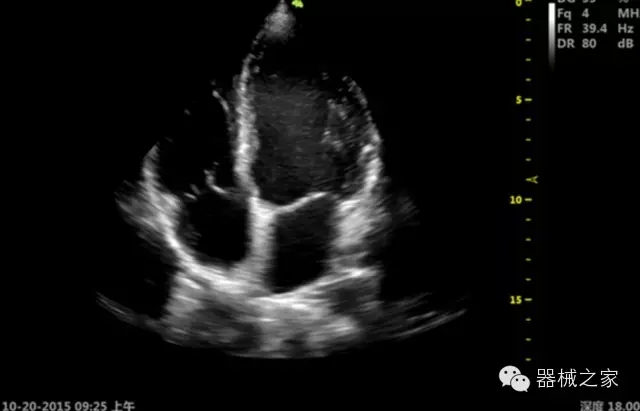

臨床圖片賞析

產(chǎn)品特點

·獨有的RF平臺提高微小細節(jié)顯示、圖像對比度和邊界清晰度;

·特有的XCEN探頭,超寬的帶寬,表現(xiàn)更高分辨率和對比度;

·單晶純凈波探頭提供更佳的穿透力和彩色敏感度;

·完整的3D/4D臨床應用,STIC, MCUT 和Auto NT等滿足產(chǎn)科所有應用;

·更高的HQ羊膜腔鏡成像技術精細觀察每一個暗區(qū)細節(jié);

·智能的觸摸屏界面,能任意角度方位旋轉3D圖像,以及注釋快速標記,提供直觀與便捷的操作,提高了工作效率;

介入室/手術室

·Needle Enhancement 穿刺增強技術,清晰顯示穿刺針尖,定位目標精確穿刺;

·智能的聲控功能,以及全屏顯示真正意義上解決醫(yī)生術中應用;

Xcen探頭技術

·獨有的Xcen高頻18MHz探頭,使微小病灶的顯示成為現(xiàn)實,為臨床提供了更廣泛的臨床應用;

·Xcen超寬頻帶探頭技術比常規(guī)探頭頻寬提高了30%,具有更廣泛的臨床應用,更高的頻率讓我們獲得了更好的細微分辨率和對比度的圖像;

肌骨理療

·智能感知組織特異性的VTissue技術,結合特有高達22MHzXcen線陣探頭, 以及獨有敏感的RF射頻血流提供了優(yōu)異臨床圖像;

·智能的教學操作流程提供全面及專業(yè)的操作步驟指導,便捷藍牙傳輸保障信息流暢;

便捷傳輸功能

·藍牙傳輸/ WIFI 郵件/ 移動網(wǎng)絡/ DICOM;

·ICU/CCU;

·飛依諾特有心臟純凈波探頭提供更好的穿透力和彩色敏感度,以及結合TView梯形拓展改善困難病人深部組織成像;

·獨有RF敏感血流使得心臟血流完美呈現(xiàn);